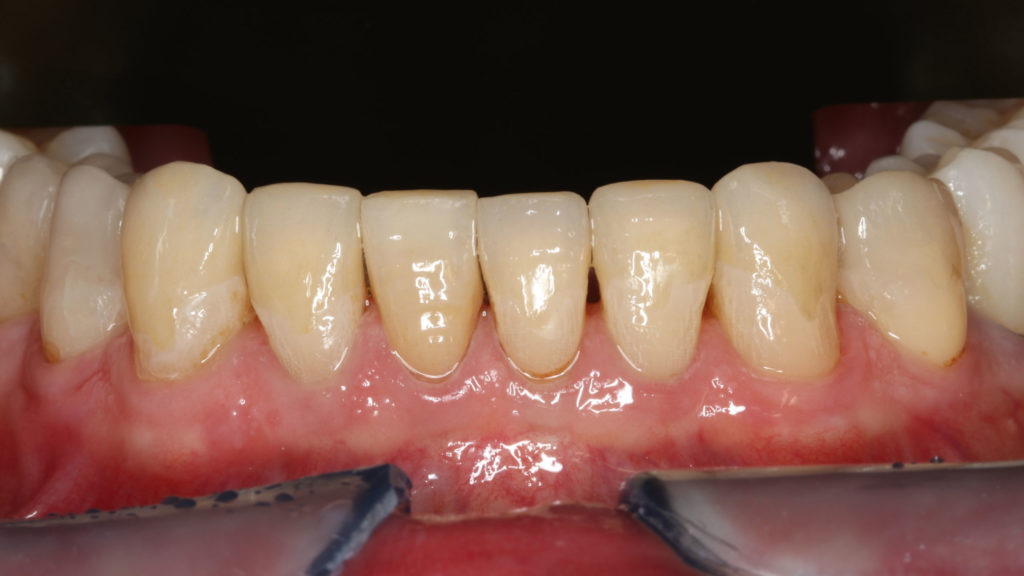

Im Labor konnten die vollkeramischen Restaurationen in der Presstechnik hergestellt werden (Abb. 8 bis 11). Die exakte Bisshöhe wurde zuvor im Mund evaluiert. Herstellung und Eingliederung der Veneers gestalteten sich dank des Wellenschliffs deutlich einfacher als mit anderen Veneer-Präparationsarten, da die Restaurationen am Zahn eine definierte Position hatten. Die adhäsive Eingliederung folgte den bekannten Abläufen. Die keramischen Restaurationen wurden geätzt beziehungsweise für das Verkleben konditioniert (Abb. 12). Nach dem Reinigen der Zähne wurden die Oberflächen mit Phosphorsäuregel vorbereitet, abgespült und getrocknet, mit Primer vorbehandelt, und es wurde Haftvermittler beziehungsweise Bonder aufgetragen (Abb. 13 bis 17). Nach dem Applizieren des Befestigungsmaterials konnten die Restaurationen eingegliedert und Materialüberschüsse entfernt werden (Abb. 18 und 19). Nach der Lichthärtung wurden die Ränder geglättet und die approximalen Kontakte angepasst sowie final poliert (Abb. 20 bis 24). Dabei zeigte sich ein weiterer Vorteil des Pfullinger Wellenschliffs. Der Übergang zwischen Zahn und Keramik ist dank des „diffusen“, bewusst unregelmäßig angelegten Präparationsdesigns optisch kaum wahrzunehmen. Eine Kontrolle der funktionellen Gegebenheiten bildete den Abschluss der prothetischen Therapie. Die in der Initialphase stabilisierte neue vertikale Bisshöhe konnte 1:1 mit den keramischen Restaurationen übernommen werden (Abb. 25).

Grundsätzlich ist es bei einer solchen Therapie unverzichtbar, während der prothetischen Phase die neue Bisshöhe zu erhalten. Daher wurde wie im ersten dargestellten Fall zunächst der Oberkiefer präpariert, mit Provisorien versorgt und im Unterkiefer die Schiene wieder eingegliedert. Nach der therapeutischen Phase wurden im Labor die vollkeramischen Restaurationen hergestellt. Während im vorangegangenen Fall indirekte temporäre Kompositrestaurationen („Deckel“) für die Unterkiefer-Frontzähne im Labor erstellt worden waren, kam in diesem Fall – aufgrund des vergleichsweise geringen Platzangebots – die direkte Methode zur Anwendung. Nach dem Einsetzen der vollkeramischen Restaurationen im Oberkiefer diente ein im Labor auf der Basis eines Wax-ups hergestellter Silikonschlüssel (transparentes Formteil) dem Herstellen temporärer Chairside-Restaurationen aus lichthärtendem Komposit. Der Patient testete in den folgenden Wochen die Situation und die neue Bisslage. Danach erfolgte die Präparation der Zähne im Unterkiefer. Die Zähne 46, 47, 35, 36 (Implantat), 37, 38 wurden für die Aufnahme von Kronen und 44/34 sowie 45 für Teilkronen (mit vestibulärem Wellenschliff) vorbereitet und die Frontzähne im Sinne eines optimalen Substanzerhalts nach dem „Pfullinger Wellenschliff“ präpariert (Abb. 27). Zahn 41 hatte bereits eine Krone, weshalb dort die Präparation nur leicht angepasst worden ist. Bei diesem Fall wurde ein reduzierter Wellenschliff vorgenommen. Das Herstellen der keramischen Restaurationen sowie die adhäsive Eingliederung folgten dem im Fall 1 beschriebenen Vorgehen (Abb. 28 bis 34). Erneut spielte der Wellenschliff seine Vorteile aus: vereinfachtes Handling in Praxis und Labor, geringe Invasivität sowie aufgrund des unregelmäßig verlaufenden Präparationsrands diffuser, augenscheinlich nicht sichtbarer Übergang zwischen Zahn und Keramik.